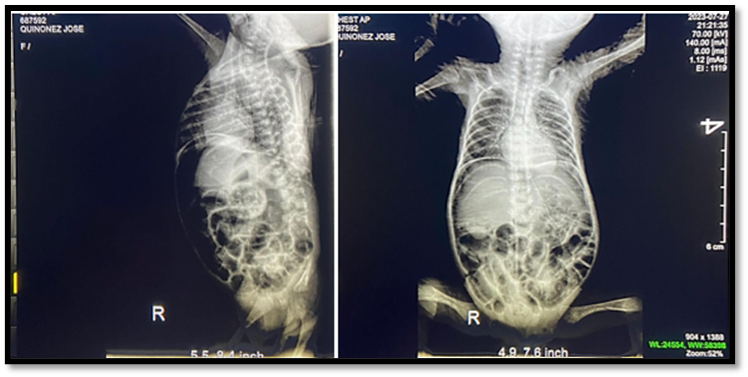

El primer dia de hospitalizacion se realizan examenes de laboratorio y se procede de forma inmediata a solicitar Rx de abdomen para confirmar diagnostico de perforacion intestinal. Se evidencian asas intestinales distendidas con imagen sugestiva de perforacion mas neumatosis intestinal. (figura 1)

Figura 1. Rx de Abdomen

Reporte: Asas intestinales distendidas que van hacia línea media, más neumatosis intestinal, neuomoperitoneo.